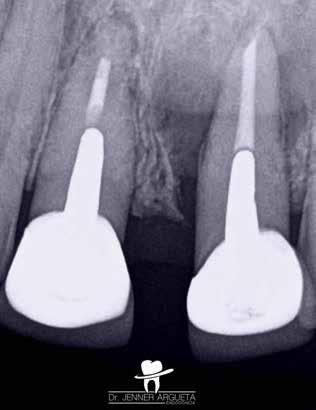

1. ábra: A 15-ös foggyökér meziális felszíne mellett látható radiolucens elváltozás, illetve a felvételen látható a korábban behelyezett gyökértömés, a parapulpális csap segítségével elhorgonyzott csonkfelépítés és a fogat borító cirkonkorona. –2. ábra: A saggitalis irányú CBCT-metszeten jól megfigyelhető az állcsontgerincet elérő radiolucens elváltozás. – 3. ábra: Az axiális irányú CBCT-metszeten egyértelműen látható a kezeletlen palatinális gyökércsatorna, valamint a radiolucens elváltozás mezio-disztális kiterjedése is jól megítélhető. – 4. ábra: A palatinális gyökércsatorna szelektív endodonciai kezelése során először gyógyszeres zárás került behelyezésre. – 5. ábra: A gyógyszeres zárás során alkalmazott kalcium-hidroxid alapú paszta a szulkuszon keresztül a szájüregbe extrudálódott. – 6. ábra: A gyökértömő anyag a középső és apikális gyökéri harmad határán lévő laterális csatornán keresztül a periapikális térbe extrudálódott. 7. ábra: A kezelések befejezését követően 4 évvel készült röntgenfelvételen jól látható a csontállomány gyógyulása és a fiziológiás gyökérhártyarés újbóli kialakulása. –8. ábra: A peroperatív CBCT-felvétel alapján készített koronális irányú metszeten jól látható a gyökércsúcs körül lévő periapikális felritkulás. – 9. ábra: A kezelések befejezése után 4 évvel készített CBCT-felvételen a gyulladásos lézió teljes megszűnése észlelhető.

A CBCT-készülékek endodonciai alkalmazásának talán az az egyik legnagyobb előnye, hogy így olyan anatómiai struktúrák is láthatóvá válnak, amelyeket egyébként nem tudnánk detektálni panoráma, cephalo, vagy periapicalis felvételek segítségével. Mivel a CBCT-felvételek kiértékelése számítógép segítségével történik, így a felvételek vizsgálata során lehetőségünk van az adott területet több nézőpontból és több síkban is megvizsgálni. 2015 októberében egy korábban a rendelőnkben kezelt 55 éves férfi páciens azzal a céllal kereste fel ismét a rendelőnket, hogy másodvéleményt kérjen egy jobb felső kvadránsban található fogával kapcsolatban. Egy másik rendelőben történő vizsgálat során a panaszos fog törését vélelmezték és a fog eltávolítását javasolták, illetve arról is beszámolt, hogy az elmúlt hét során ezen a területen egy puha duzzanat is kialakult. A klinikai vizsgálat során a jobb felső első és második kisőrlő között (14–15) egy fluktuáló duzzanatot észleltünk az áthajlásban. Az 15-ös fog mesialis oldalán 12 mm mély tasakot szondáztunk. A páciens által hozott periapicalis felvételen a 15-ös fog gyökércsúcsának mesialis részén egy nagy kiterjedésű radiolucens elváltozás volt észlelhető (1. ábra). A saggitális síkban vizsgált CBCT-felvételen (Carestream CS 9000, Carestream Dental) a lézió valódi kiterjedése is láthatóvá vált (2. ábra). A megelőző endodonciai kezelések során csupán a bukkális csatorna került detektálásra és gyökértöméssel való ellátásra. Az axiális irányú CBCT-szeleteken egyértelműen látható volt az ellátatlan palatinális gyökércsatorna (3. ábra)

Először kalcium-hidroxid alapú ideglenes gyógyszeres zárás került a palatinális csatornába (UltraCal XS, Ultradent Products; 4–5. ábra), amelyet 6 hét után a végleges gyökértömés elkészítése előtt eltávolítottunk. A gyökértömés elkészítése során meleg vertikális kondenzációs technikát alkalmaztunk. Radiológiai felvételen megfigyelhető volt, hogy a gyökértömő anyag egy laterális csatornán keresztül kis mennyiségben a periapicalis térbe extrudálódott (6. ábra). A 4 évvel később készített kontrollfelvételeken a lézió gyógyulása volt megfigyelhető (7–9. ábra). A vizsgálati eredmények és a kezelés kimenetele egyértelműen igazolta, hogy nem gyökérfraktúrával álltunk szemben, tehát a kezdeti diagnózis tévesnek bizonyult. Ez is azt erősíti, hogy korlátozott mennyiségben rendelkezésre álló adatok alapján nem lehet pontos diagnózist felállítani. Manapság szinte elengedhetetlen a CBCT-felvételek endodonciai beavatkozások során történő használata, feltéve, ha ezek elkészítése során az ALARA elv (as low as reasonably achievable) betartásra kerül.